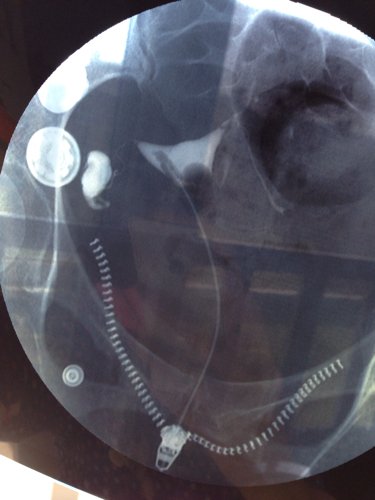

两年前我做过宫外孕腹腔镜手术,前几天去做了输卵管造影,做腹腔镜那侧不通另侧积水!我应该怎样治疗! 点击展开 匿名用户 2014-03-22 23:33 为您推荐: 其他回答 病情分析: 您的情况应该是输卵管炎症的表现。 指导意见: 可考虑通水治疗。把舌头的照片发一张过来看看。可考虑请中医大夫看看,选用中药如桂枝茯苓丸、当归芍药散、妇炎康来调治。 虞静涵_slGJ 2014-03-23 05:02 相关问题 我去年得过一次宫外孕做过一次腹腔镜手术 现在输卵管堵塞还有积水 医生又建议做腹腔镜手术 会影响吗 宫外孕腹腔镜手术后是否需要做输卵管造影? 宫外孕腹腔镜手术时医生说另一侧输卵管是通的,我还需要做造影检查吗